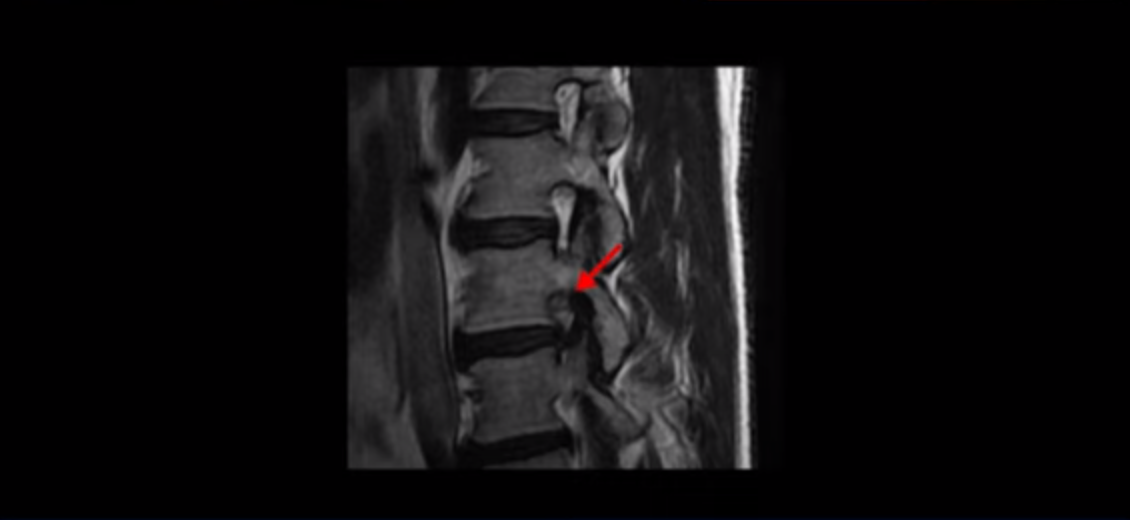

이 환자분 말씀 잘 들으셨습니까? 이분 MRI를 보면 3번과 4번 디스크가 심하게 파열되어 밀려나온 수핵이 위로 밀려 올라가 있습니다. 수핵이 위로 밀려 올라가면서 디스크 본체와의 연결이 끊어져 있습니다.

일반적으로 이런 형태의 밀려나온 수핵이 끊어진 디스크 파열이 훨씬 더 흡수가 잘 됩니다. 그 이유는 뒤에 설명해드리겠습니다.

이분은 오른쪽 허리부터 엉덩이와 허벅지 및 발까지 방사통이 극심하고 감각기능도 떨어졌는데요. 보시다시피 오른쪽 신경 나가는 구멍이 밀려나온 디스크 수핵 때문에 좁아져서 어둡게 보입니다.